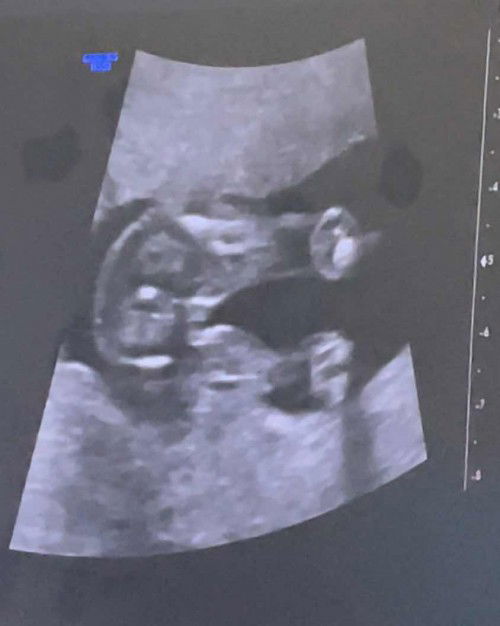

Boy or girl

Hi ultrasound of my 17weeks old baby, is it a boy or a girl?😊❤️